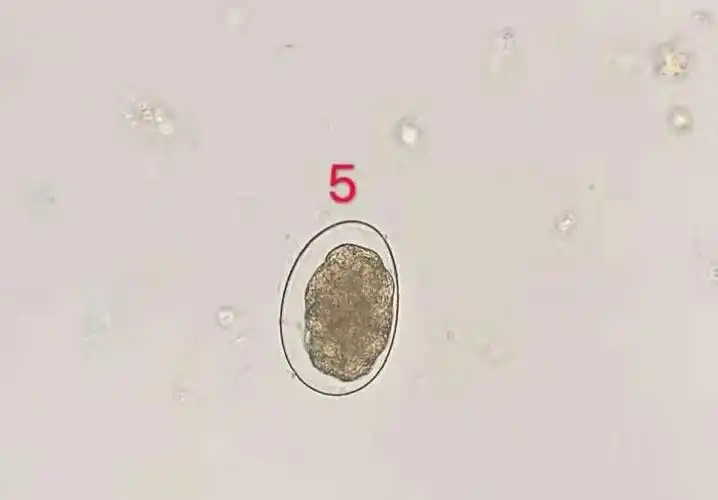

寄生虫——18级检验二班郑钰洁

寄生虫形态·常见寄生虫卵

寄生虫虫卵图片